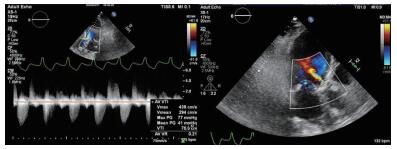

2 实例分析案例:病史摘要:患者为70岁老年女性,因“反复胸闷气促3月余,再发加重3 d”入院。患者2020.3.10从本科急诊途径入院,入院时呈端坐呼吸,伴大汗,本科急诊医生快速完成新冠肺炎核酸检查及肺部CT检查排除新冠肺炎感染后收住心内科监护室。患者既往病史复杂,高血压20年余,糖尿病20年余,2年前曾因冠心病在当地医院行经皮冠状动脉介入(percutaneous coronary intervention,PCI)治疗。入院查体:神清,精神软,呼吸急促,无法平卧,口唇无发绀,颈静脉无怒张,两肺听诊闻及大量湿啰音,心率98次/min,律齐,主动脉瓣听诊区可及4/6级舒张期吹风样杂音,双下肢可见凹陷性水肿。入病房后相关检查提示:“氨基端B型利钠肽原>35 000 pg/mL,肌钙蛋白T 0.139 ng/mL,血肌酐192 μmol/L,血气分析:二氧化碳分压44.7 mmHg(1 mmHg=0.133 kPa)、氧分压65.5 mmHg、氧饱和度90.1%”,心超提示“左室舒张末期内径(LVEDD)5.81 cm,simpson's测得LVEF 33.5%;主动脉瓣呈三叶结构,瓣叶增厚明显,主动脉瓣口最大射流速4.39 m/s,最大压差77 mmHg,平均压差41 mmHg,瓣口面积0.57 cm2” (图 1)。临床诊断考虑:①心脏瓣膜病:主动脉瓣重度狭窄急性心功能不全Killip Ⅲ期;②冠状动脉粥样硬化性心脏病PCI术后;③高血压病;④ 2型糖尿病糖尿病肾病。予以静脉呋塞米利尿等对症治疗后症状无缓解。患者主动脉瓣重度狭窄诊断明确,本次严重症状考虑与原发瓣膜病相关,有TAVR手术治疗指征。但患者病情危重,无法完成血管入路、冠脉及主动脉增强CT检查,本院心脏瓣膜团队讨论后决定行急诊TAVR治疗。

| 图 1 患者术前超声心动图 |